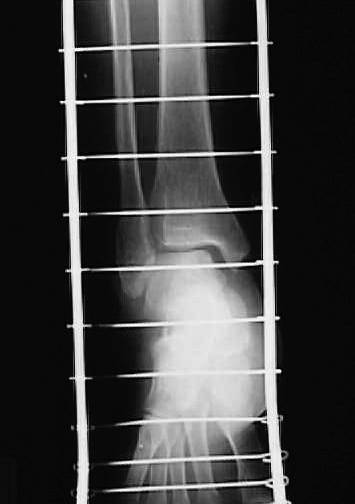

X線撮影依頼(図5、6)。患者に自発痛はなく全身症状の経過は良好であったが、X線診断の結果、整復が不十分と判断し、前日同様の再徒手整復を行う。骨折部の整復状況を触診にて確認し、問題ないと判断した後、再度前日同様に固定する。

図5

図6